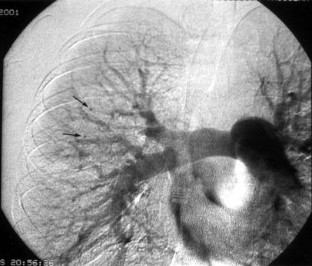

Fig. 1